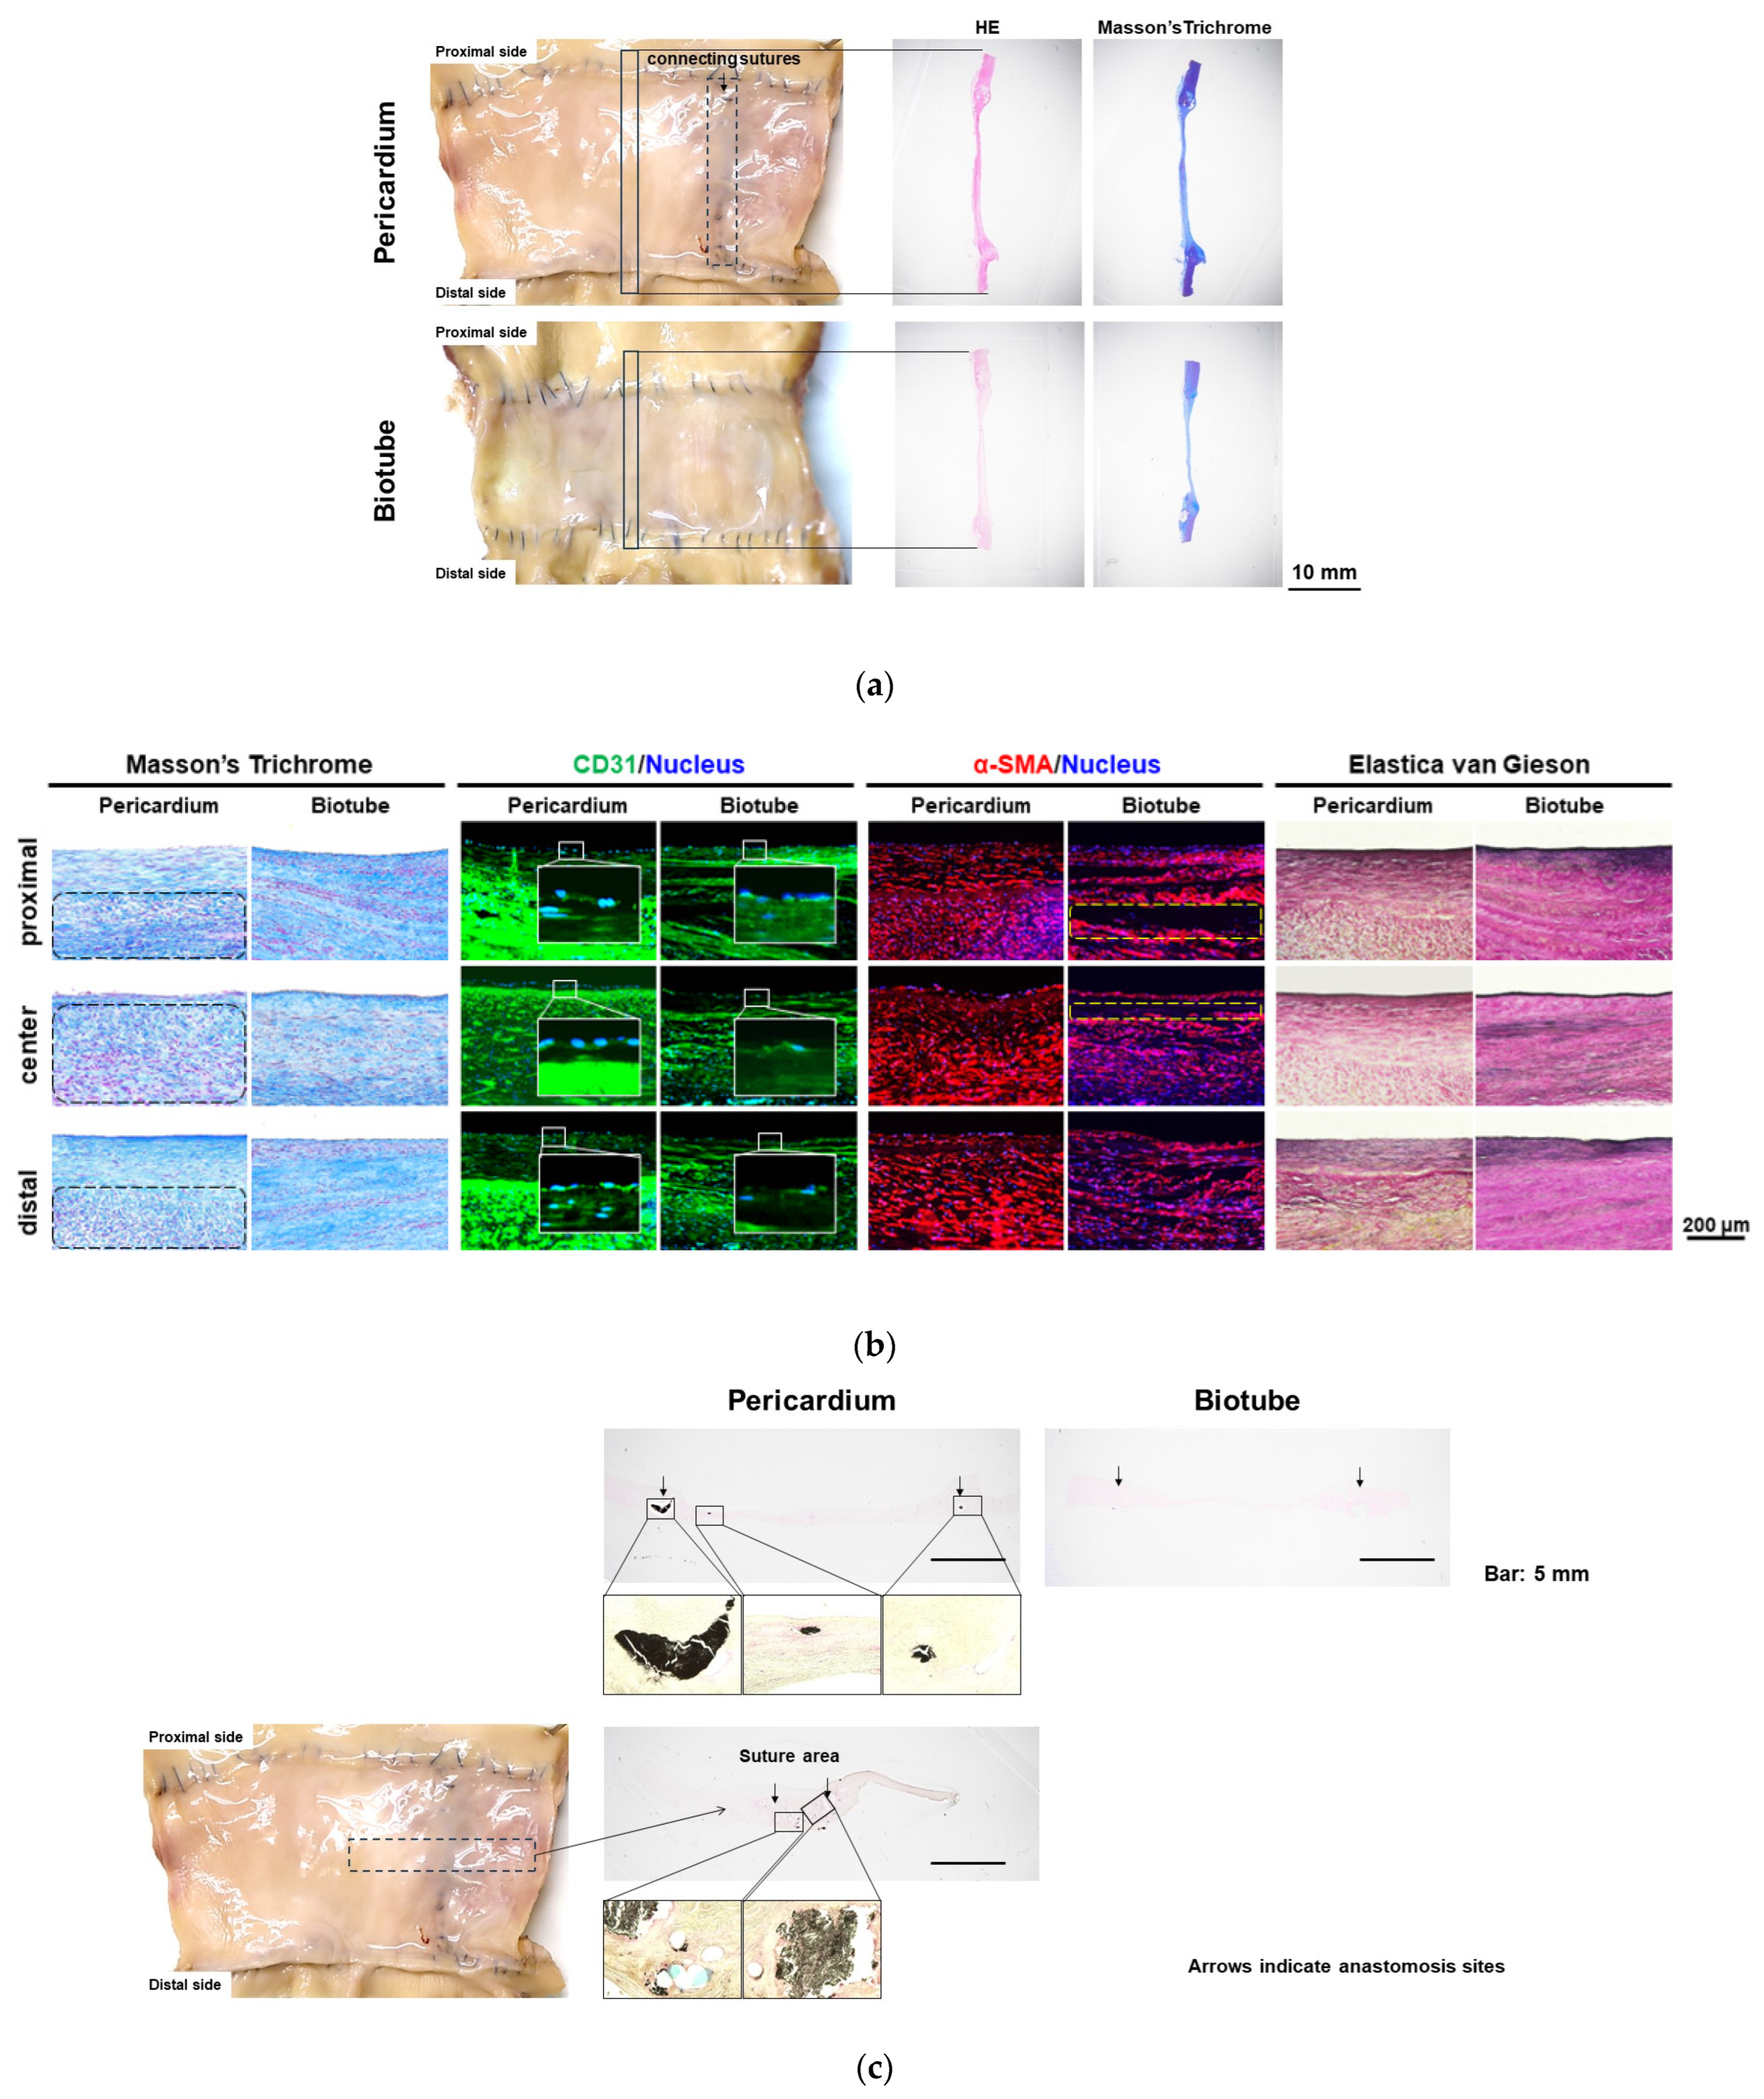

3.2. Image Evaluation

3.3. Histologic Evaluation

4. Discussion